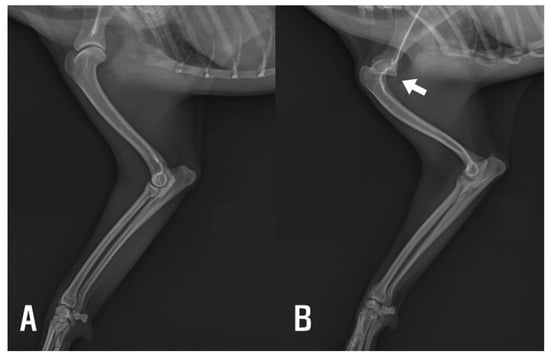

Radiographic evaluation revealed dysplasia of the left scapular glenoid cavity and humeral head, supporting a diagnosis of congenital shoulder luxation (Figure 1). Advanced imaging, such as CT or MRI, was not performed due to the owner’s decision; however, given the absence of elbow osseous abnormalities on radiographs, the restricted ROM observed clinically was considered consistent with periarticular soft tissue contracture.

Figure 1. (A) Right forelimb showing normal glenohumeral joint alignment. (B) Left (affected) forelimb demonstrating displacement of the humeral head consistent with flattened glenoid cavity (arrow).